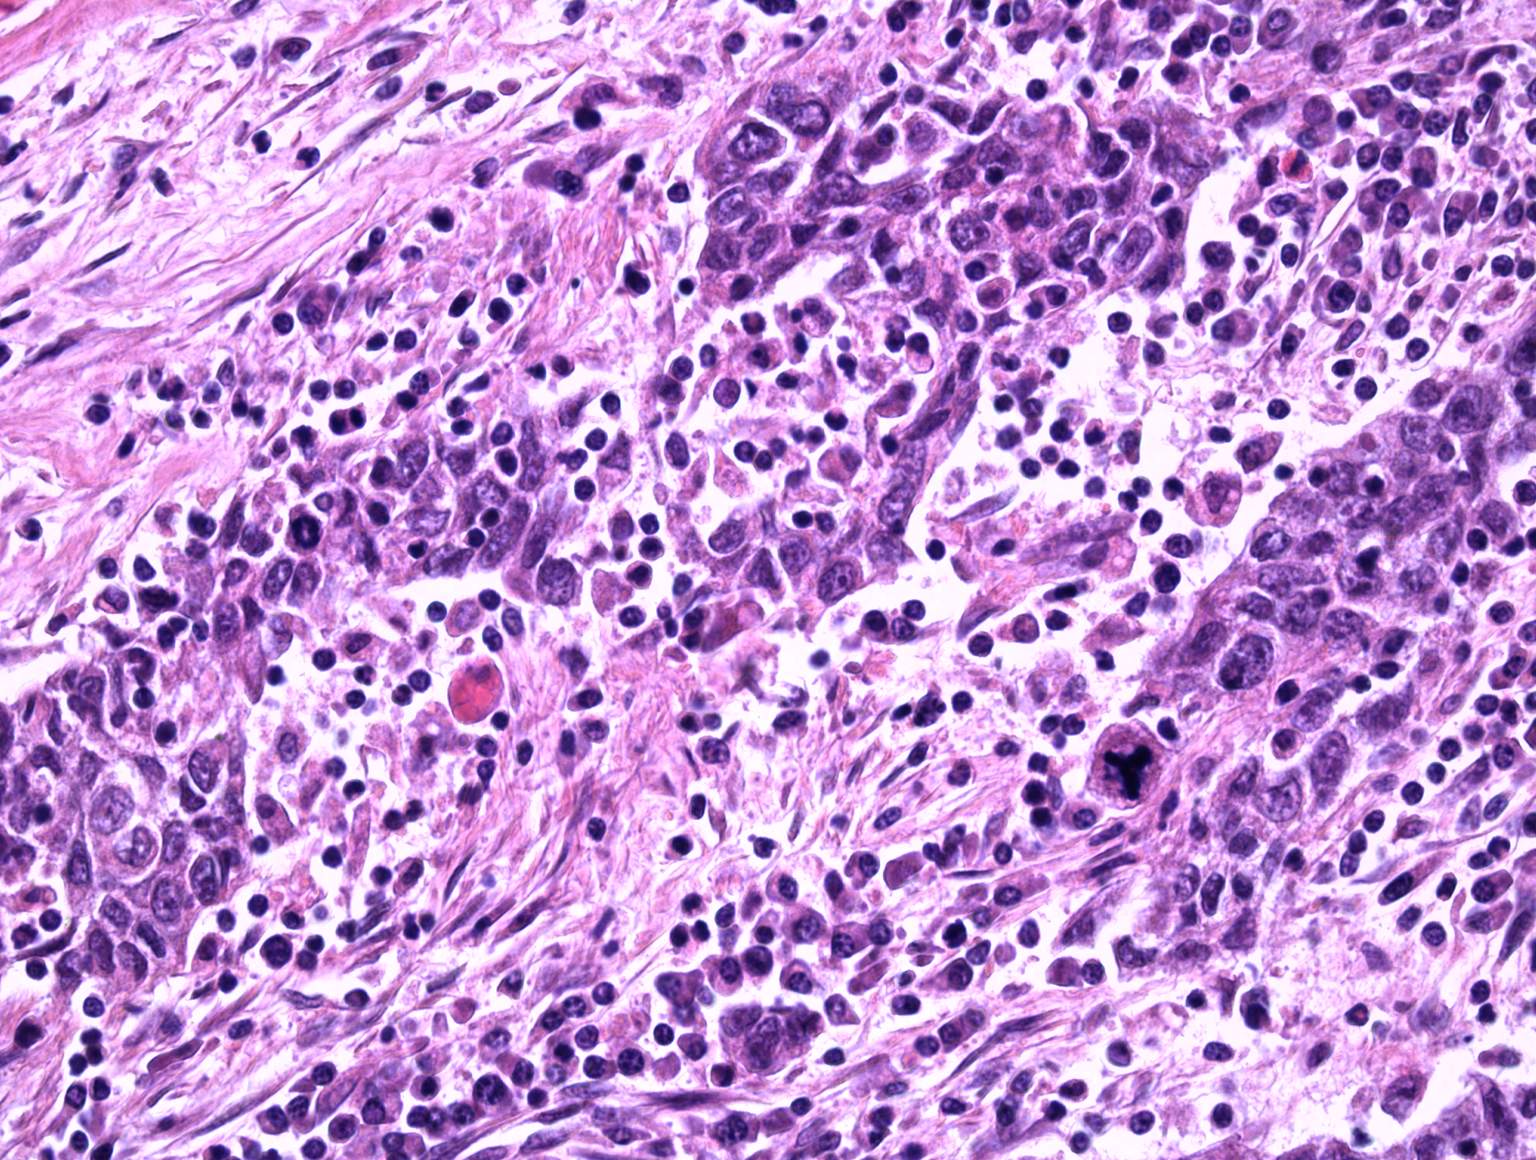

Undifferentiated carcinoma with ductal and

adenosquamous component

detail: x10

Undifferentiated carcinoma